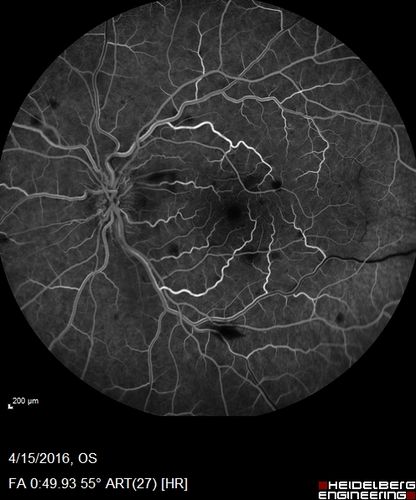

Central retinal artery and vein occlusion - Protein C Deficiency 33 year old male

33 year old male with vision loss for 3 hours.  VA 20/12 right eye, 5/200 left eye.  He has a protein C deficiency.  The left eye recovered vision in about 1 month to 20/16.  FA shows very slow recirculation time.